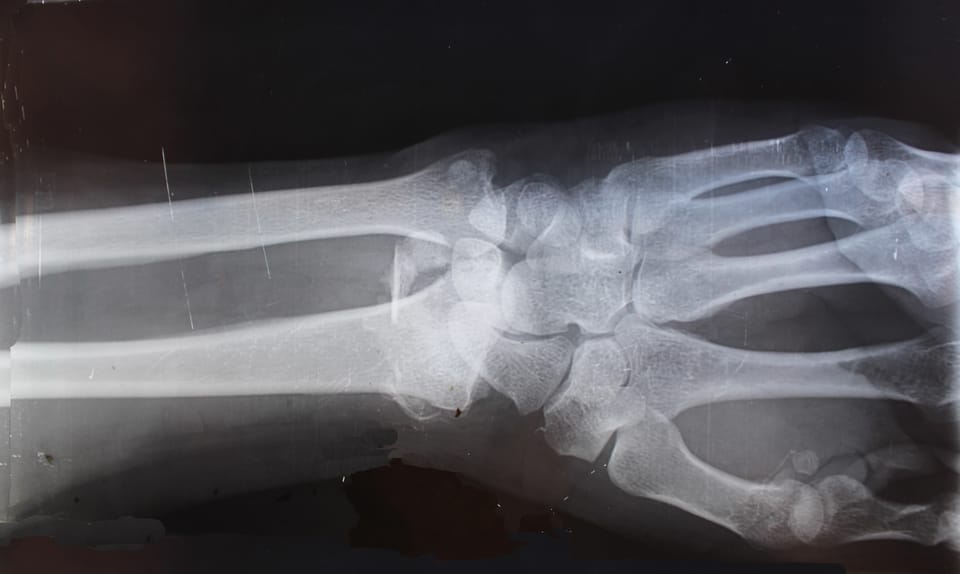

Dual-energy X-ray absorptiometry (DEXA) is commonly referred to as a bone density test. It is most often used to diagnose osteoporosis, a condition that causes bones to thin and become more fragile, and osteopenia, or low bone density. The test can provide a great deal of valuable information about the condition of your bones and the likelihood that you will experience a break.

If you come to Iowa Radiology for a DEXA scan, plan for a 30-minute appointment, about 10 minutes of which will be the actual scan. Be sure to avoid calcium supplements for at least 24 hours before the test. During the exam, you will lie on your back on a padded table, over which an X-ray arm will move as it gathers images. Typically, you will be asked to lie still in two different positions in order to take images of your hip and lower spine. There are no restrictions following this test, so you are free to immediately resume your normal activities. We will have a report of the results to your physician within one business day.